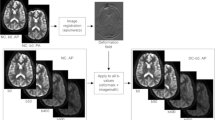

Example bone metastasis illustrating effect of B0 inhomogeneity induced distortion on DWI. In each subfigure, the slice corresponds to the horizontal slice at which the lesion is the largest (see “Methods” section). The orange bounding box was drawn 10 voxels from the lateral edge of the lesion (in DWI space) in each of the 4 directions, then overlaid on the other images. (A) DWI b = 0 s/mm2 image acquired in the forward phase encoded direction. (B) DWI b = 0 s/mm2 image acquired in the reverse phase encoded direction. (C) Estimation of the distortion within the slice. Voxel values represent the extent of displacement undergone by each voxel. Red and blue values denote displacement in the posterior and anterior direction, respectively. (D) DWI b = 0 s/mm2 image after DisCo. (E) T2-weighted image at the same slice. DisCo distortion correction.

Examples of bone metastases as seen on b = 0 s/mm2 DWI pre-and post-DisCo. The top row (A–D) shows a vertebral lesion in the Thorax Station. The bottom row (E–H) shows a lesion within the left femoral head in the Pelvis Station. (A,E) T2-weighted images at the corresponding level with an orange bounding box drawn around the lesion. (B,F) T2-weighted images zoomed in to visualize lesion and surrounding area. (C,G) Zoomed in DWI b = 2000 s/mm2 and b = 0 s/mm2 images before DisCo, respectively. (D,H) Zoomed in DWI b = 2000 s/mm2 and b = 0 s/mm2 images after DisCo, respectively. Outlines of the lesion annotations are overlaid in red. In both examples, the lesions were translated anteriorly following DisCo. Without DisCo, lesion localization may have erred posteriorly. DisCo distortion correction.

To explore the extent to which B0 inhomogeneity may induce geometric distortions, we plotted example lesions from different parts of the skeleton and in different imaging stations (Figs. 2, 4). The metastasis in the left femoral head shown in Fig. 4E–H, for example, underwent B0 inhomogeneity-induced contraction, as can be appreciated with the dark strip of voxels at the anterior edge of the lesion in Fig. 4G. Additionally, the right clavicular lesion included in Fig. 2 became more globular in shape and was partially rotated after application of DisCo.